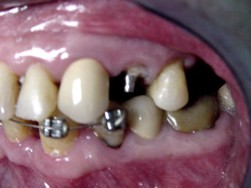

Paciente masculino, de 61 años de edad, presenta pérdida de la corona clínica del 24 por caries de recidiva, que se extiende subgingivalmente hacia mesial, a más de 2mm por debajo de la cresta ósea (Fig.4 y 5), imposibilitando tanto por razones estéticas como técnicas, la realización de una cirugía periodontal para ganar corona clínica y, de esta manera, realizar la preparación de la línea de terminación de la futura prótesis fija.

Fig.4 Foto inicial. Vista lateral

Fig.5 Vista oclusal

Se procedió a la colocación de brackets estándar 0.018 x 0.030 de slot, en 22, 23, 24 y 25. Los brackets en 22,23 y 25 se cementaron a la misma altura sin tomar en cuenta la posición o rotaciones de los dientes y el bracket del 24 se cementó lo más gingival posible para tener rango de movimiento en sentido vertical.

Se colocaron 2 arcos seccionales: el arco base 0.016x 0.016 de acero que unió los brackets del 22,23 y 25 (anclaje); y un arco 0.014 de níquel-titanio, el cual se ligó sobre el otro arco y se llevó hasta el bracket del 24. Este arco es el que produjo el movimiento de extrusión del diente (Fig.6 y 7).

Fig.6 Colocación de doble arco

Fig.7 Vista oclusal